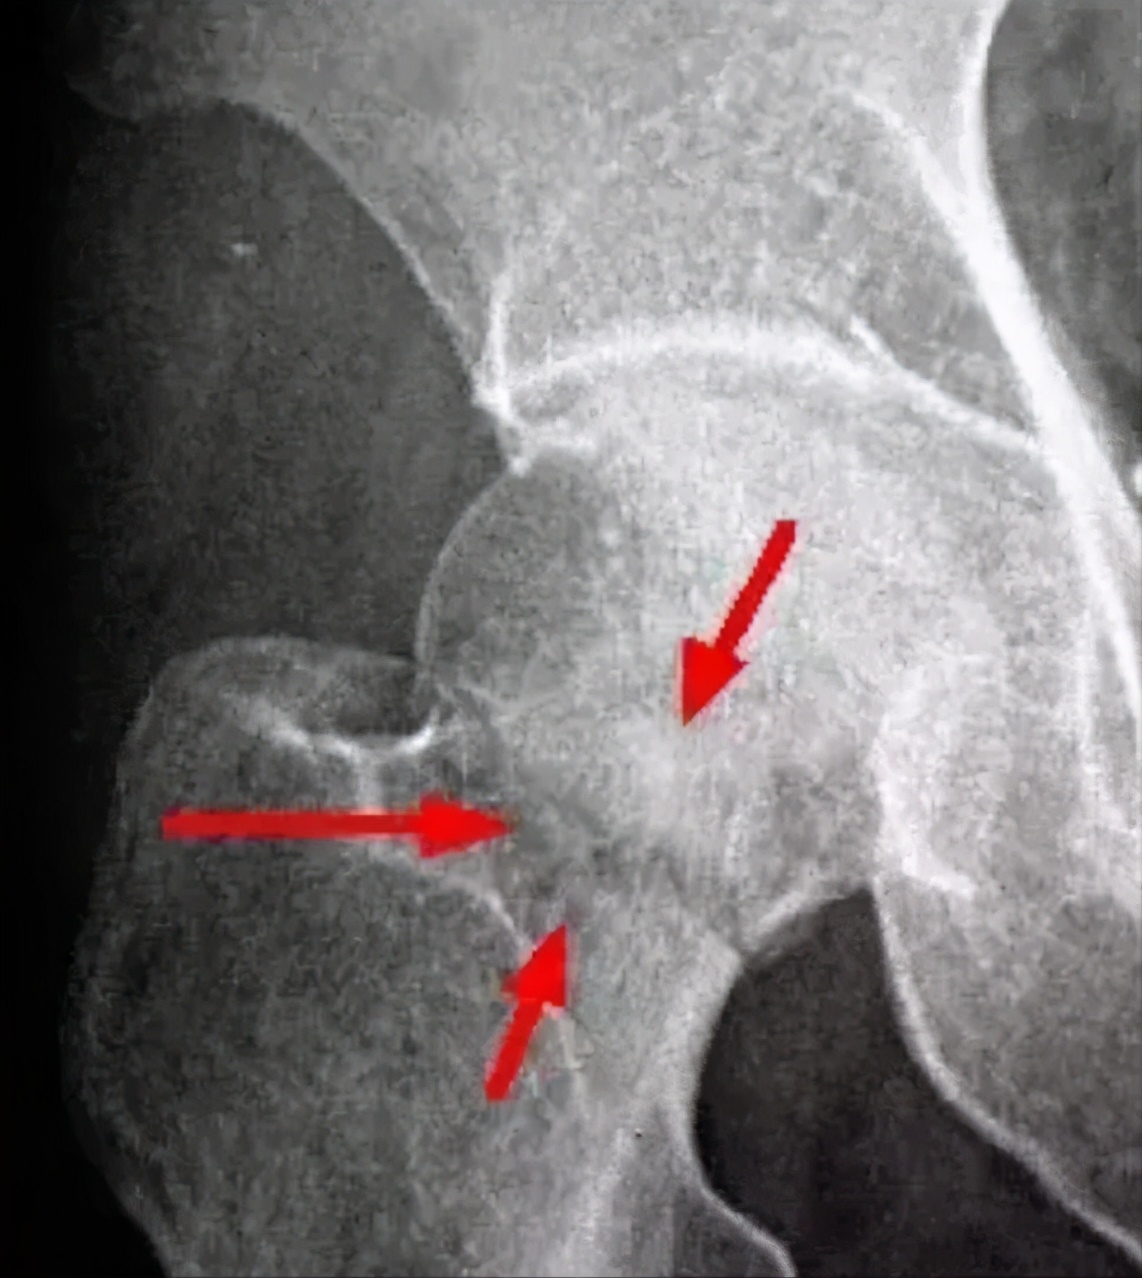

治疗前:右股骨头负重区不完整,缺损,可见大量坏死区,骨密度不均匀。